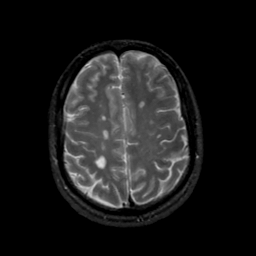

MR Study #17, July 7, 1991 -- Slice #37